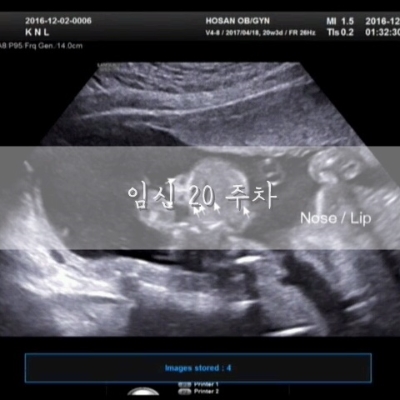

임신 20주 :: 정밀초음파, 임신 6개월 증상

임신 20주 증상아랫배 통증 폭풍태동 정밀초음파 소화불량 자도자도 졸려요 몸무게 47.3kg(+3kg) 혈압 119/...